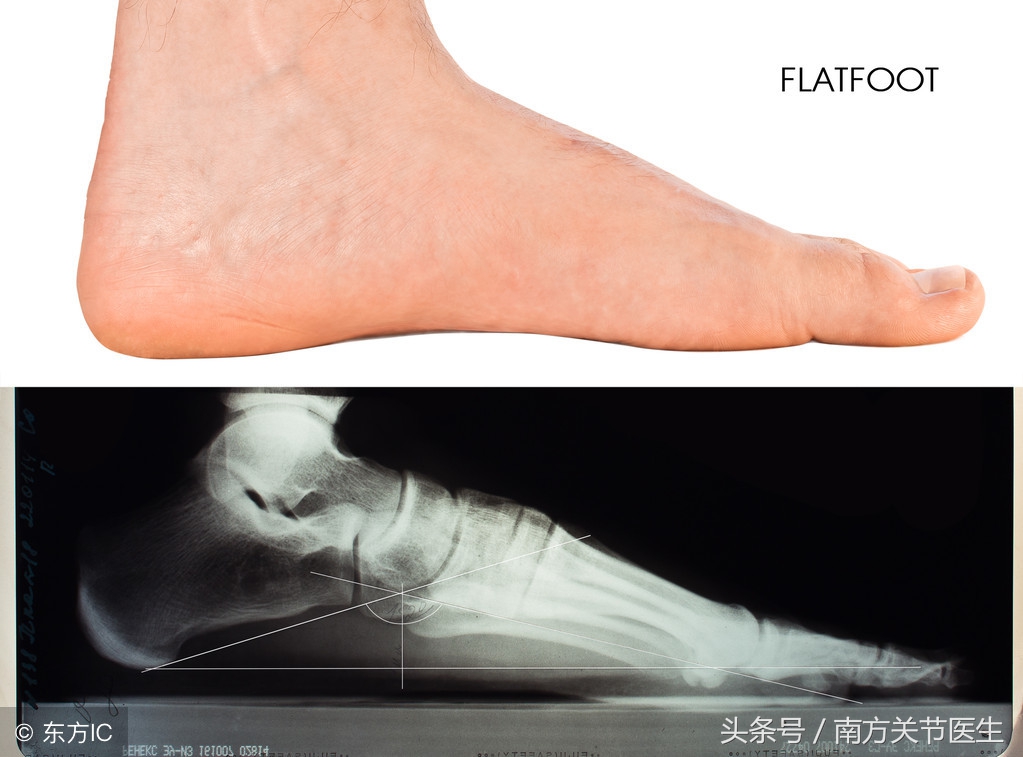

帆布鞋不适合长期穿,因为对脚部的危害很大。这种鞋子的鞋身很柔软。穿上后,会感觉到脚很舒服,但是由于后跟和中底部厚度不够,使得稳定性不高。由于稳定性不够,会影响足部的健康发展,对儿童的足部影响较大。长期穿这种鞋子可能会导致儿童患扁平足。若是扁平足患者长期穿这种鞋子,则不能预防该疾病的后遗症,而且会导致足弓变形。若是胶质的鞋底,则避震性不强。在要进行长时间运动,最好不要穿这种鞋子。

不要长期穿帆布鞋,特别是年龄较小的孩子。长期穿帆布鞋可能会导致扁平足,所以偶尔穿穿就好。

总结一下,帆布鞋很好搭配,也很时尚,但是不能长期穿。对于足部还在发育的孩子,长期穿帆布鞋会导致扁平足。在做剧烈运动的时候,也不建议穿这种鞋子。预防扁平足需要做好以上六点。穿鞋有讲究。参加不同的运动穿不同的鞋子,不要只穿帆布鞋。